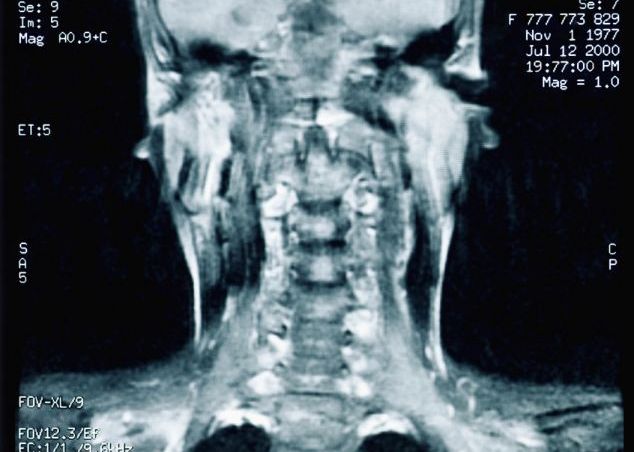

Neurochirurgia ar fi ajuns la performanta transplantului de cap, primele incercari fiind facute pe maimute. Primele operatii pe primate (1970, 2001) n-au fost reusite pentru ca nu s-a putut face "conectarea" dintre creierul donatorului si coloana vertebrala a primitorului.

Capul pregatit pentru transplant trebuie sa aiba o temperatura intre 12 si 15 grade Celsius. Se crede ca asa zisa "conectare" a capului donatorului cu trupul primitorului nu trebuie sa dureze mai multde o ora. Foarte mult dureaza, insa, "calibrarea" coloanei vertebrale a primitorului cu creierul donatorului, existand, fireste, mai multe "sanse" de nereusita.